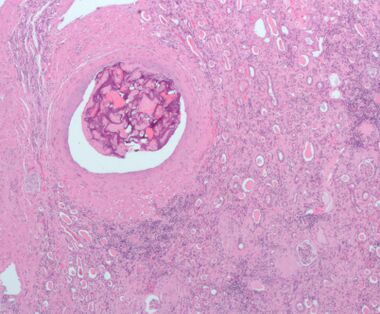

![]() Micrograph of embolic material in the artery of a kidney. The kidney was surgically removed because of cancer. H&E stain. | |

- أورام الكلية